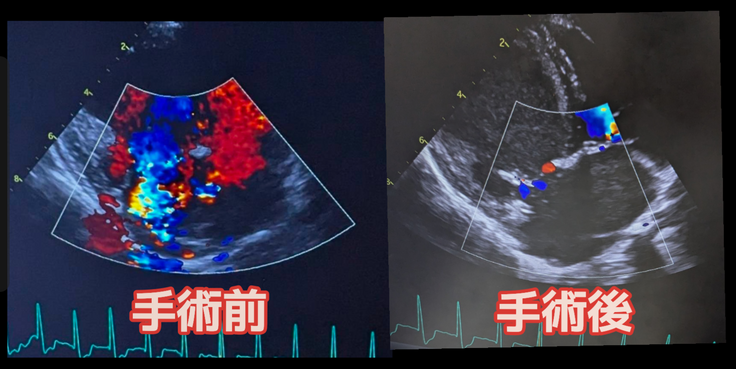

血栓、免疫異常、血小板数値など色々と難しい話は多かった中で、素人目でも手術効果が分かりやすかったのはエコー検査の結果でした。

簡単にいうと、心臓の血流を「赤」と「青」に色分けして平常であれば弁を挟んで色がくっきり分かれるのですが8割が逆流していた虎太郎は赤青以外も含め複数の色が映っておりましたが、術後は明確に血流が変化していました。

※病院から掲載許可は頂いております